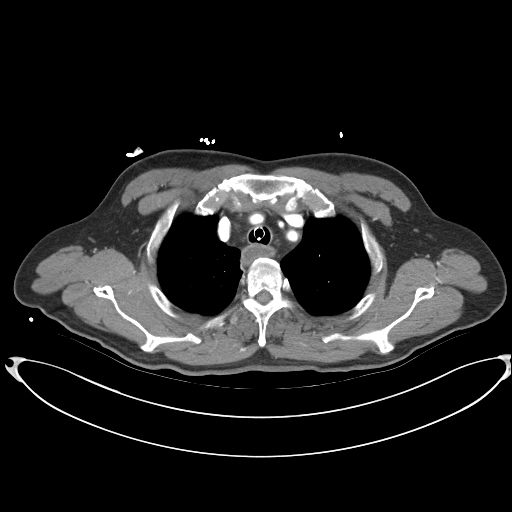

- CT(컴퓨터 단층촬영) : X선을 여러 각도에서 촬영해 컴퓨터로 재구성한 단층 영상을 얻는 검사입니다. 촬영 속도가 매우 빠르고, 폐, 복부 장기, 골절 진단에 탁월합니다.